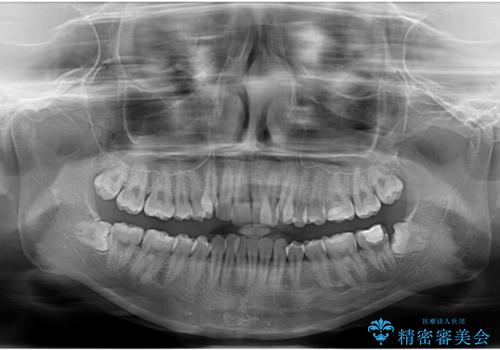

上顎前歯部はデコボコが強く、歯を並べるためのスペースが不足しているため、左右の第一小臼歯を抜歯することとしました。

また、抜歯して確保したスペースが不足してしまうのを防ぐため、補助装置を併用しています。

矯正治療の前に上下左右の親知らずの抜歯も行いました。